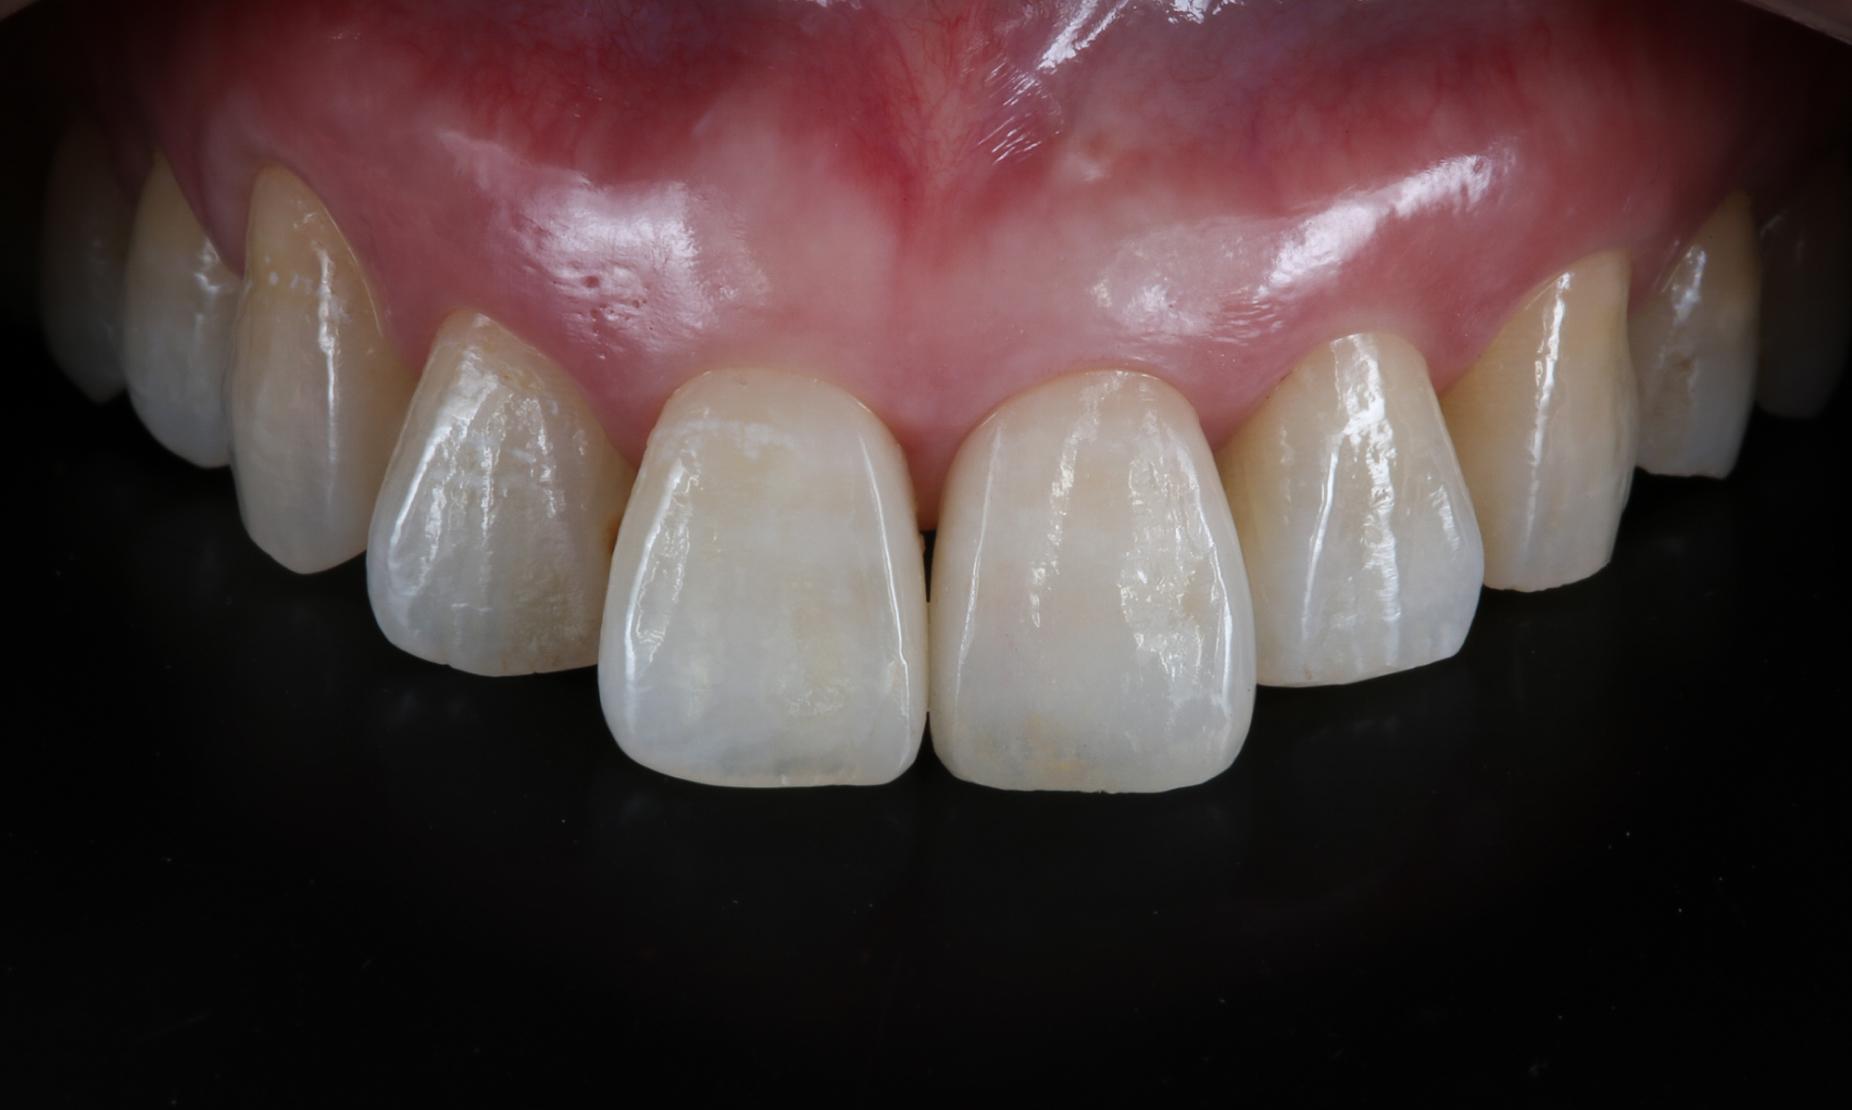

上の前歯6本の中で1本だけインプラントが入っています。どの歯がインプラント=作り物の歯か分かりますか?当院の高度歯科医療ではここまで自然な歯に仕上げることが可能です。

完成写真

最終的に、どこにインプラントがあるのか分からないほど自然な仕上がりとなりました。